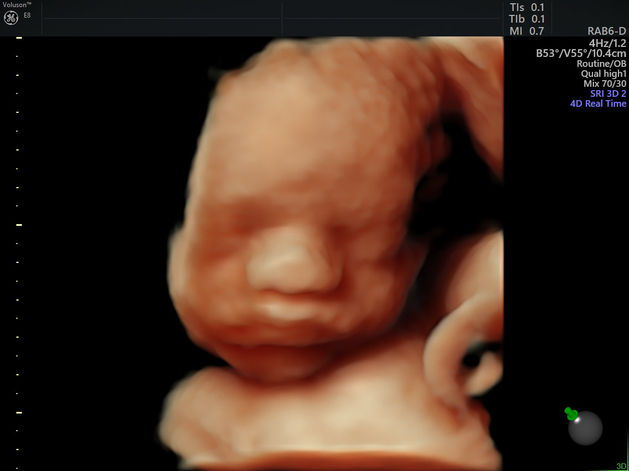

For our first baby, Chloe and I were having what many would consider the ideal pregnancy. There had been no morning sickness and no complications. Our world changed on March 13th when we received a call regarding the results of our 20 week scan. While sitting in an airport halfway across the country waiting on a delayed flight, we were told that our son Devereaux's heart was to the right, his stomach was midline, and that his kidneys were misshapen. With no more information than that, we were told that we would be contacted by a high risk pregnancy specialist in Tulsa, OK. One week later at the Perinatal Center in Tulsa it was confirmed that our precious baby boy had CDH, but on the bright side, closer inspection revealed that his kidneys looked normal. After moving forward with an amniocentesis, no further genetic abnormalities were found. That very day we were referred to Johns Hopkins All Children's Hospital in St. Petersburg, FL. On April 12th, just one month after receiving our life-changing call, we arrived at JHACH for our preliminary appointment with Dr. Kays and his team. One of the first things that Dr. Kays said was, ”we are going to fight, and we are going to win!” What a powerful and uplifting statement to begin this journey on! We were given a 90%-95% chance of survival, with a 20%-25% chance of needing ECMO, which exceeded our expectations based on the research we had done beforehand. His heart, although on the extreme right side of his chest appears to be fully developed and functioning properly. The hole in the diaphragm is considered large, and the stomach, intestines, spleen, and 10-15% of the liver have made their way into the chest cavity and are impeding on the lungs. Fortunately, our little fighter is still growing, measuring in the 76 percentile and meeting normal benchmarks, including practicing breathing.